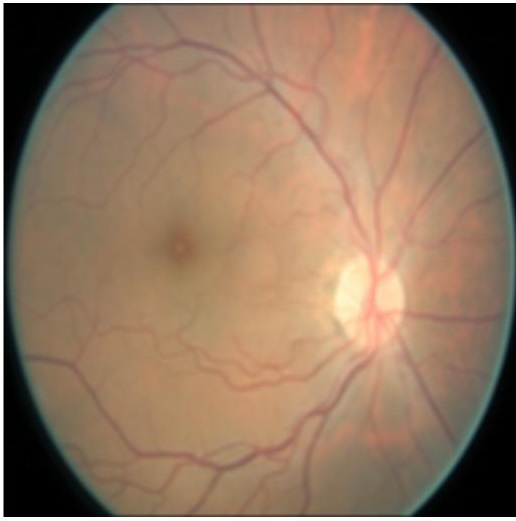

Figure 4 (a) shows an example retinal image followed by its ground truth manual segmentation in Figure 4 (b). Figure 4 (c) shows segmentation result for scaling factor when using the original HR images to train the U-Net followed by the results when trained on the super resolved images generated by , (Figure 4 (d)), (Figure 4 (e)), (Figure 4 (f)), SR-RF (Figure 4 (g)), SSR (Figure 4 (h)) and (Figure 4 (i)). Obviously the results from provide results most similar to those of HR images. This is also validated by the quantitative results in Table 3. The areas where different methods are unable to obtain accurate segmentation are highlighted by yellow arrows. Due to poor quality of super resolved images most of the methods do not segment the finer vasculature structures, while SSR and SR-RF are unable to segment some of the major arteries. Importantly, our method performs much better than the low resolution image () which performs poorly due to low resolution.

![]() |

| (a) | (b) | (c) | (d) | (e) |

| (f) | (g) | (h) | (i) | (j) |